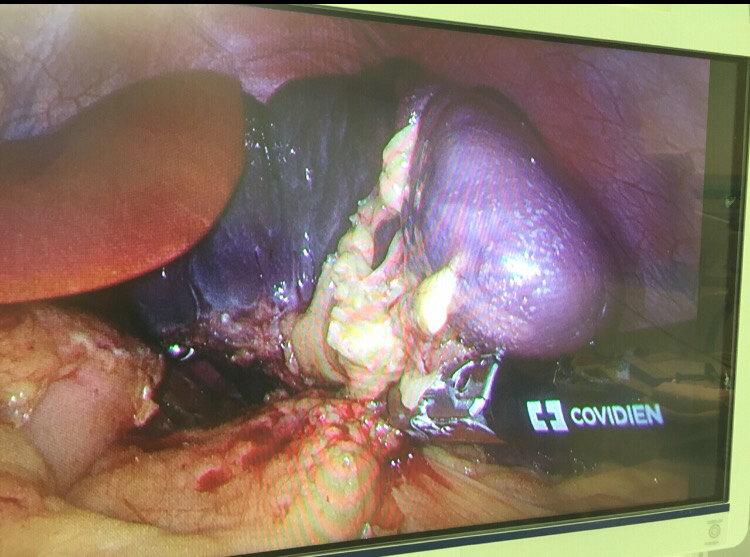

腹腔镜切除脾脏

我院微创中心主要开展微创切脾手术。与传统开腹手术相比,具有安全、创伤小、疼痛轻、并发症低、住院时间短、腹壁疤痕小、术后肠道功能恢复快,肠粘连几率低等优点。相应的,对手术医师的技术要求也非常高,既要创伤小,又要将脾脏完整切除,在手术过程中发现胆囊结石也一并解决,医师要有丰富的经验才能把握好这个“度”。我们医院作为上海开展腹腔镜脾切除最多的医院,在微创脾切除手术方面积累了丰富的经验,也是全国开展该类手术病例最多的医院中心之一,并且无一例死亡病例。